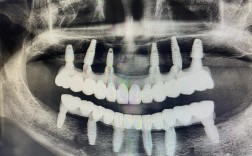

- 影像学检查:

- 锥形束CT: 这是必须的! 可以精确测量缺牙区牙槽骨的高度、宽度、密度,观察上颌窦位置、下颌神经管位置,评估骨缺损的具体情况,是制定种植方案和选择植骨方式的金标准。

- 全口曲面断层片: 作为初步筛查和整体评估。